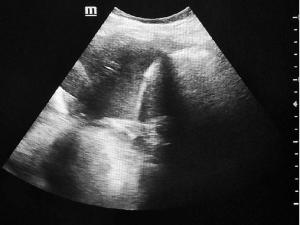

A spontaneous inferior epigastric artery rectus sheath hematoma is a rare condition where bleeding occurs within the sheath of the rectus abdominis muscle, often due to damage to the inferior epigastric artery or its branches. We present an adult case of giant spontaneous left inferior…...